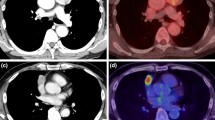

Figures 3 and 4 show representative 18F-FDG PET-CT images of baseline and post-treatment scans in a patient with metabolic response and a patient with metabolic progression of the disease, respectively. The responding patient of Fig. 3 was allocated in the class of PR using RECIST and showed a 47% reduction of tracer uptake indicating a concordance between morphologic and metabolic tumor response. Conversely the non-responding patient of Fig. 4 was judged to have stable disease by RECIST but he showed a 64% increase of 18F-FDG uptake indicating a metabolic progression.

Representative images of baseline a and post-treatment b 18F-FDG PET-CT scan in a patient with thymic carcinoma. Fusion images of co-registered transaxial 18F-FDG PET and contrast-enhanced CT sections are shown. In the baseline scan SUVmax was 6.60 whereas the post-treatment study showed a SUVmax of 3.50. A 47% reduction of 18F-FDG uptake was found in this patient with partial response based on RECIST. The same maximum threshold of SUV was applied to PET images from pre-treatment and post-treatment scans as shown by the color scale on the left

Representative images of baseline a and post-treatment b 18F-FDG PET-CT scan in a patient with thymic carcinoma. Fusion images of co-registered transaxial 18F-FDG PET and CT sections are shown. In the baseline scan SUVmax was 8.80 whereas the post-treatment study showed a SUVmax of 14.40. A 64% increase of 18F-FDG uptake was found in this patient with stable disease based on RECIST. The same maximum threshold of SUV was applied to PET images from pre-treatment and post-treatment scans as shown by the color scale on the left